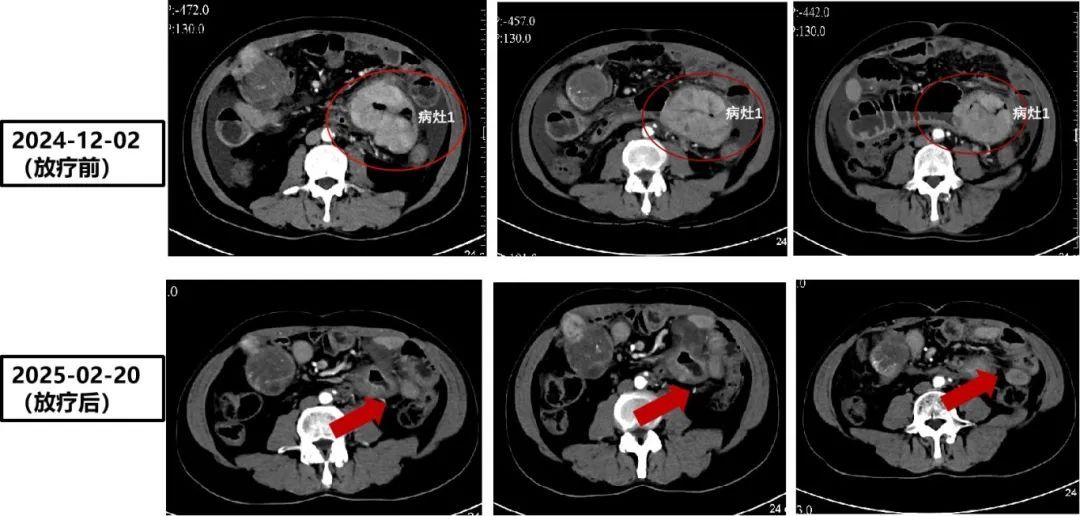

近日,一位历经七年抗癌治疗的患者银先生,将一面绣着“医术精湛 悬壶济世 医德高尚 妙手仁心”的锦旗送至南方医院肝脏肿瘤中心。这份致谢背后,是南方医科大学南方医院肝癌多学科诊疗(MDT)团队以匠心医术和温暖仁心,点亮患者生命之灯的感人故事。命悬一线,三次病危通知书下的坚守42岁的银先生7年前年初体检发现肝脏占位,进一步检查发现肿瘤指标AFP升高,考虑原发性肝癌,及时在我…